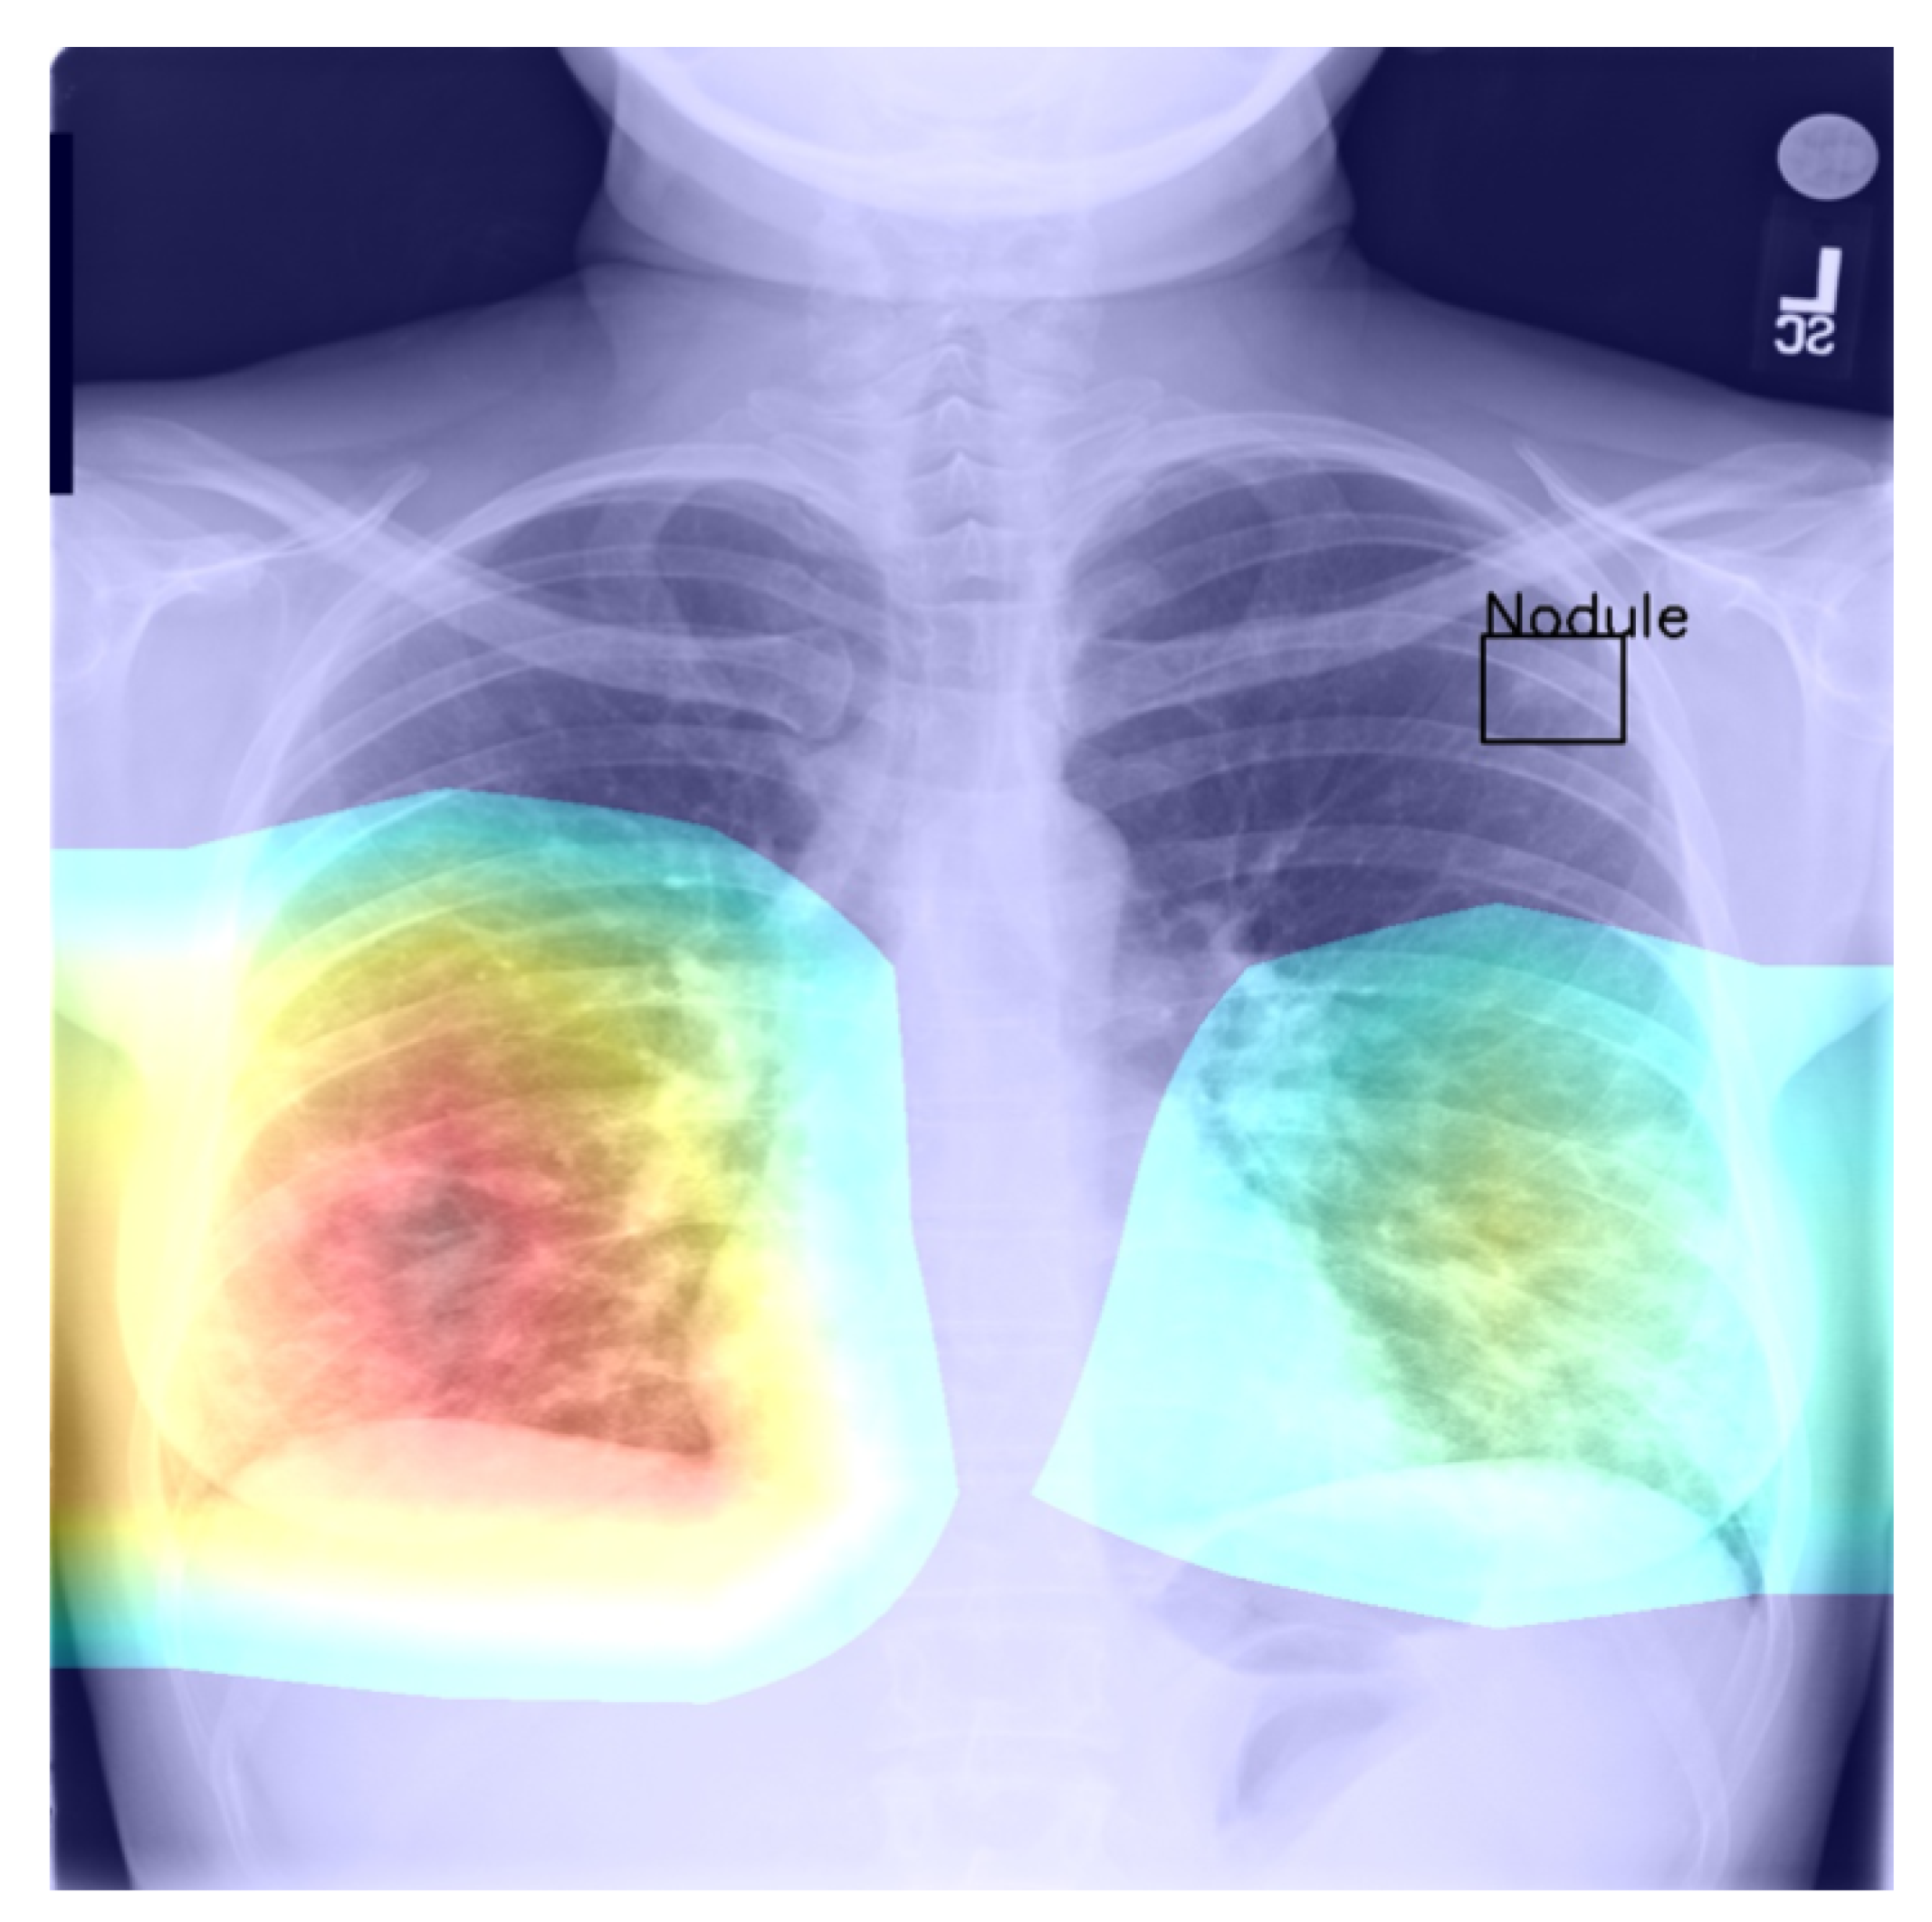

4.4. Saliency and Explainability

As we noted previously, using Grad-CAM, or indeed similar methods [27], it is possible to quantify and thus visualise the importance of different parts of an analysed image a network uses as the basis for its prediction. This can be helpful both in understanding why the model fails when it does as well in focusing an expert’s attention for further analysis and interpretation.

Using the bounding boxes information provided, we further examined how well the models performed in localizing the visual presentation of different diseases. We quantified this using the intersection over union (IoU), a ratio of the intersection of the bounding box and heat map activation and the union of the area they both cover, which can be loosely related to the well-known Bhattacharyya coefficient, a measurement of the amount of overlap between two statistical samples [28,29]. The ratio was calculated using thresholded heat maps with the key findings summarised in Table 6 and Table 7.

These findings are interesting in the context of the previously discussed AUROC-based comparison. Although the modified model performed better in terms of the former performance measure, that is to say AUROC, here, we found that it is the standard that does a better job in localizing the diseases. The likely explanation for this apparent paradox can be found in the structure of the network that was introduced in Section 3 and shown in Figure 1 and the flow of the metadata information and the manner in which it is used in the backpropagation. In any event, the important lesson to draw here is the same one that pervades the present article: any model must be examined in a variety of different ways and its performance measured using a range of comprehensive metrics and with a keen eye on their clinical significance, and its failure modes must be identified and understood, before any application in the real world is even considered.

Returning to the findings in Table 6 and Table 7, it is a concerning fact that the minimum IoU for all classes was found to be zero (an interesting example is shown in Figure 4. In other words, in the case of every class, that is disease, there was at least one instance in which the ground truth bounding box had no intersection with the thresholded saliency heat map. The models did, however, perform rather well in many cases, as indicated by the average scores. To check for potential biases, we measured the Pearson’s correlation coefficient between the number of class instances and the corresponding mean IoU and found it to be −0.265. This is an interesting and perhaps somewhat surprising finding, which should be revisited in future work. On the present evidence, we hypothesise that the more numerous classes exhibited greater variability in appearance presentation, which affected the performance under the IoU measure.